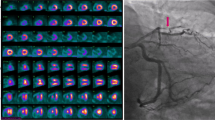

Image interpretation was independently performed by two experienced nuclear medicine physicians (XYX and MFY), and disagreements were resolved by consensus. Both observers were blinded to all other clinical information when analyzing images, but were aware of the culprit lesion by looking at the stent on the CT co-registered with PET. First, myocardial 18F-FDG uptake in the remote (non-culprit coronary dominant) region was visually graded as follows: grade A, lower than or equal to blood-pool activity; grade B, higher than the blood-pool but lower than the infarcted area; and grade C, higher than or equal to the infarcted area (Figure 2). Second, myocardial uptake was quantitatively analyzed using the commercial software package MedEx (MedEx Technology Co. Ltd., Beijing, China). In patients with grade A or B activity in the remote region, the 18F-FDG uptake volume of the infarcted area was determined by a region grow algorithm with a threshold of 50% of the maximum uptake.16 The maximum standardized uptake value (SUVmax) of the infarcted region was also obtained. In patients with grade C activity in the remote area, only the SUVmax of the infarcted area was manually measured, and the volume of the infarcted area could not be delineated. The SUVmax of the remote area was obtained by manually drawing a circle of 10 mm in diameter in the myocardium opposing the infarct zone oriented by the PET/CT fusion image (Figure 2).

Location and semi-quantitative measurement of the infarcted and remote myocardium (upper panel) and peri-coronary adipose tissue (PCAT) (lower panel) on 18F-FDG PET/CT. Myocardial 18F-FDG uptake in the remote region was visually graded. Grade A, lower than or equal to blood-pool activity; grade B, higher than the blood-pool but lower than the infarcted area; and grade C, higher than or equal to the infarcted area

For PCAT measurement, adipose tissue was identified using threshold attenuation values of − 190 to − 30 Hounsfield units. Then, a circle of 5 mm in diameter was drawn on the PCAT adjacent to the left main coronary and proximal right coronary artery (RCA) in the axial PET/CT fusion image, and the SUVmax was measured (Figure 2). The former was selected to represent the PCAT activity of the left anterior descending (LAD) and left circumflex (LCX) coronaries, and the latter represented the PCAT activity of the RCA. The circle was manually placed 1 mm away from the coronary outer wall and more than 10 mm away from aortic wall to prevent partial volume effects. Neither myocardial tissue nor the coronary vessel was included in the region of interest. In terms of the manual measurement, SUVmax of the region of interest was obtained separately in three continuous slices in the axial PET/CT fusion image and then averaged. Mean of the measurements taken by two investigators was calculated for further analysis.

18F-FDG PET/CT

By visual evaluation, most patients (31/36, 86.1%) had higher 18F-FDG uptake in the infarcted myocardium than in the remote myocardium (grade A: 26 cases; grade B: 5 cases). The SUVmax was significantly higher in the infarcted than in the remote myocardium [4.3 (3.6-5.3) vs 1.9 (1.3-2.6), P < .001] (Figure 3). PCAT activity in the culprit coronaries was higher than that in non-culprit coronaries [1.4 (1.3-1.7) vs 1.2 (1.1-1.3); P < .001; Figure 3].

18F-FDG uptake in the infarcted and remote myocardium and peri-coronary adipose tissue (PCAT). The 18F-FDG intensity in the infarcted myocardium was significantly higher than that in the remote area. The PCAT of culprit coronary arteries showed a significantly higher 18F-FDG uptake compared to that of non-culprit arteries